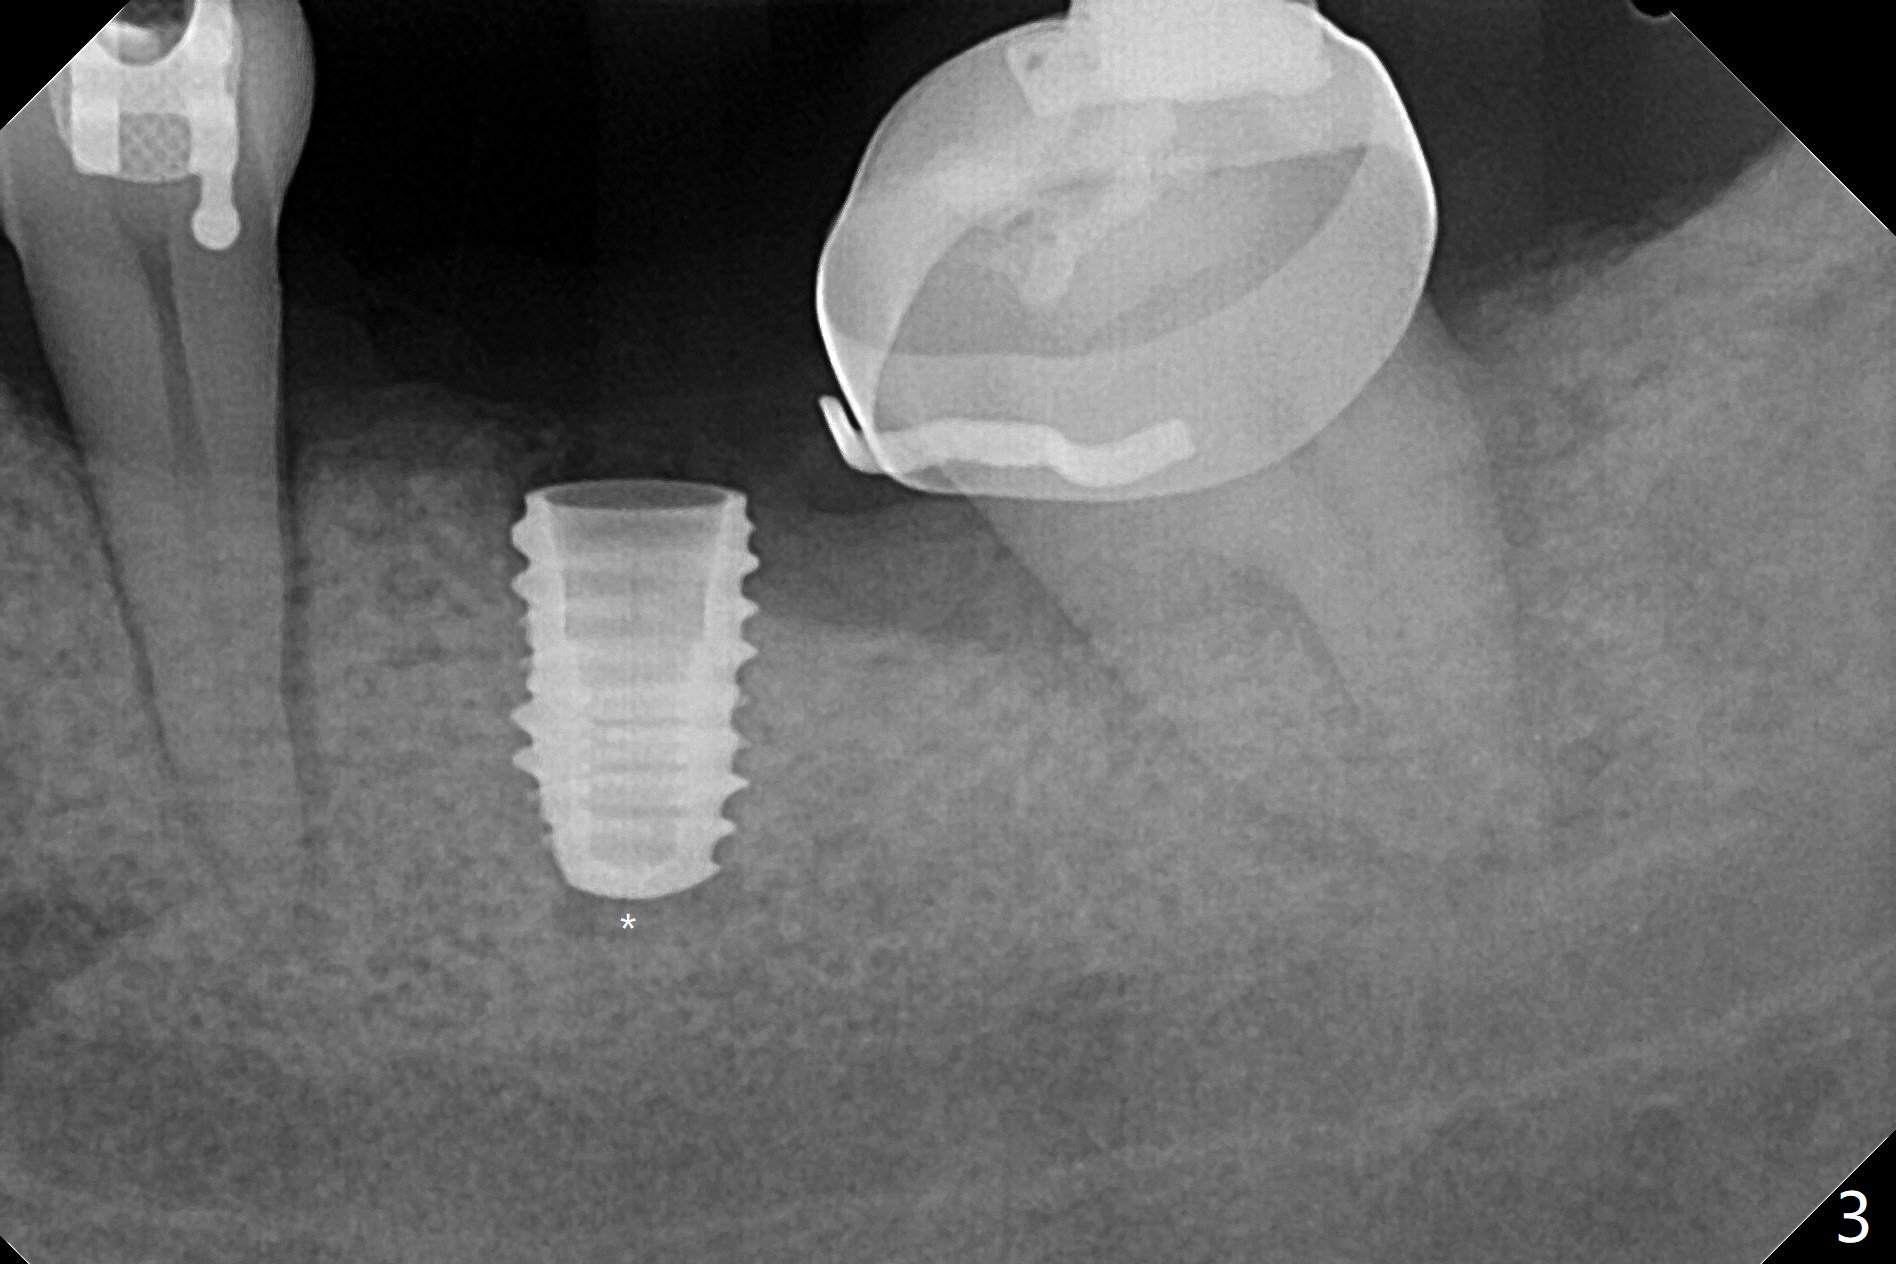

31岁女19号牙残根拔除,没有植骨,牙齿矫正创造了大约近远中10.5毫米空间,先锋钻深度8毫米(图一),远中舌侧骨质缺损(*)。使用4x7.3毫米钻头(实际长度8.5毫米)后,植入4.5x7.3毫米植体,远中大约3个螺纹暴露(图二)。使用4x8.5毫米钻头后,植体种深些(图三),但是根尖仍有空间(*)。再种深后(只有一个螺纹暴露),放置基台和粘性骨粉(图四:*),覆盖PRF,缝合,放置矫正钢丝和牙周敷料。